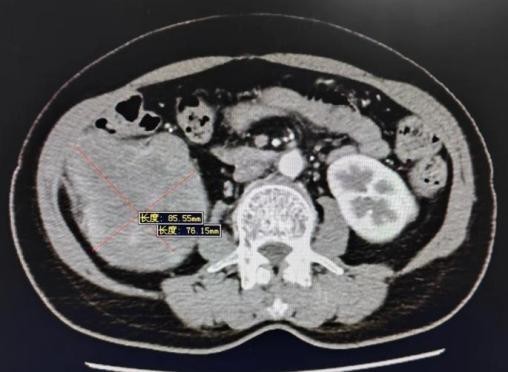

60岁的任女士(化名),2月前因无意间触及到右腰部有包块来到哈医大二院泌尿外科找到王海平教授寻求帮助。增强CT提示右肾下极12cm肿块并侵及升结肠。完善术前检查后,王海平教授请到王贵玉教授会诊。

增强CT提示右肾肿瘤截面及与结肠关系密切